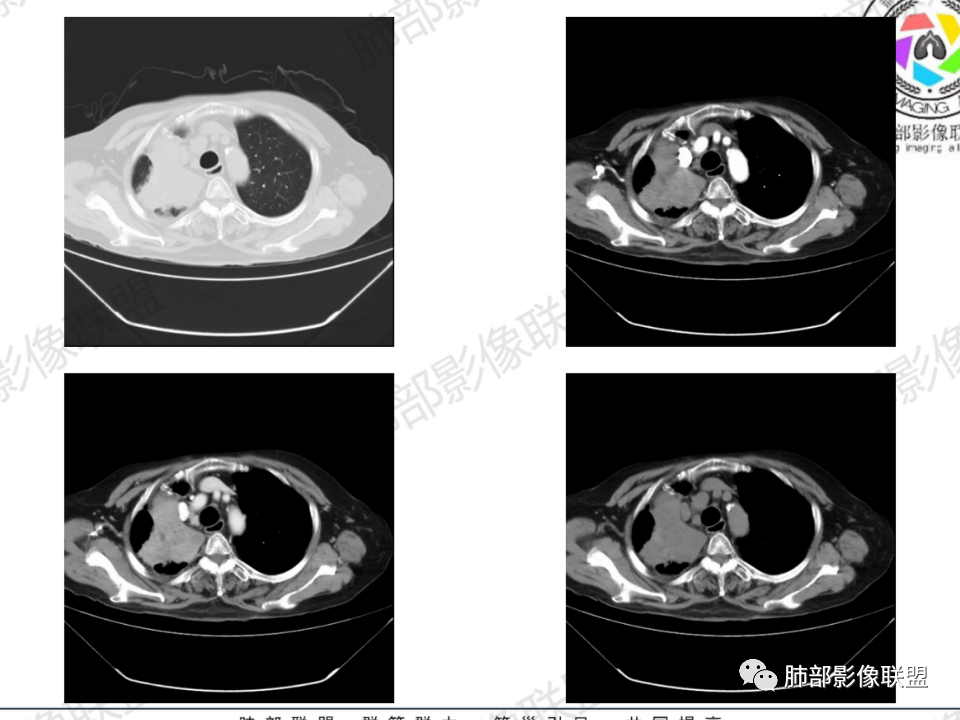

那个人:老年女性,亚急性病程,咳嗽发热。有垂体前叶功能减退,目前激素替代治疗,长期激素,量小,不知道累积量,没有目前激素水平指标。既往有淋巴结结核病史。肿瘤标记物Ca125升高。血沉升高,C反应蛋白轻度异常。影像,右肺上叶靠近肺门团块影,右肺门淋巴结钙化肿大,支气管狭窄,局部增厚,团块影外朝内改变,强化明显,血管破坏不明显,有粘液。和纵隔胸膜分界清楚,周围肺组织有斑片渗出影,右侧胸腔积液,考虑炎性?结核?支气管镜检查除外恶性飞鹰行动:老年患者,影像表现 右肺上叶占位性病变,边界清楚,有分叶征,内见细小钙化,右肺上叶支气管截断,增强病灶不均匀强化,病灶内有条状坏死区(扩张的支气管?),纵膈内未见增大淋巴结,考虑炎性病变,结核可能。一切∮随缘:右肺上叶实性肿块形态不规则,呈三角形,边缘分叶,边界伴有磨玻璃影,近段支气管未见明显显示,可能堵塞,病变平扫密度均匀,增强后可见低密度坏死无强化,周围略强化,右肺下叶散在结节。心包积液,及右侧胸腔积液,临床:有低热,低蛋白血症,肿瘤标记物高,考虑恶性:腺癌,神经内分泌癌(强化偏弱了),淋巴瘤,鉴别:结核红星:老年女性患者右肺上叶,肺门上区 分叶状肿块 ,右肺上叶支气管显示不清,增强扫描肿块,中等程度强化可见小斑片状坏死区,病灶内部可见斑点状钙化灶,病灶周围可见斑片状及小斑点状影,纵膈淋巴结增大,其他区域,胸膜下可见斑点状钙化。考虑肉芽肿性病变,结核的可能性大。老年患者最排除肿瘤性病变腺癌。土娃:右上肺不规则肿块影,边缘分叶,边界磨玻璃影欠清,病灶分叉状,内见点状钙化影及坏死灶,支气管堵塞,病灶增强强化不明显。考虑瘤样结核,鉴别淋巴瘤。张小兵:老年女性,亚急性病程,右肺上叶见不规则肿块,边缘平直凹陷为主,周围GGO边界不清,内见点状钙化及坏死灶,增强持续性渐进强化,右侧少量胸腔积液,双肺门及纵隔肿大淋巴结伴钙化,综合考虑慢性炎症。saf:老年患者,影像表现 右肺上叶占位性病变,边界清楚,有分叶征,增强病灶明显不均匀强化,纵膈内未见增大淋巴结,考虑炎性病变,结核可能。小兜:老年女性,咳嗽喘息一月,发热三天,肿瘤标志物升高,长期激素替代治疗。CT示右肺上叶近肺门不规则实变影,周围伴磨玻璃影,增强持续性渐进强化,内部血管破坏不厉害,内部可见多发条形低密度灶,右侧胸腔可见少量积液,双肺门及纵隔可见钙化淋巴结,考虑为炎性病变,结核可能玫:女,79咳嗽,喘息一月,发热三天入院,右肺上叶不规则形软组织密度肿块影,边界清晰,边缘见分叶及细短毛刺,病灶内见点状钙化影及稍低密度区,病灶边缘呈磨玻璃样改变,增强扫描,病灶呈不均匀性强化,考虑炎性病变,鉴别鳞癌。大雄:老年女性,既往诊断淋巴结结核,提示已治愈,近2年服用激素,诱导结核复燃→发热;纵隔肺门淋巴结肿大钙化,压迫支气管,右肺上中下叶支气管均狭窄→喘息咳嗽;尖段支气管受累闭塞→肺不张、支气管粘液栓;累及胸膜,结核性胸膜炎并胸水→右侧胸痛;实验室,血沉快,CA125高,低蛋白,符合;下一步,支气管镜尖段支气管刷检抗酸染色周太狼:老年女性,亚急性病程,肿瘤标志物升高。CT示右肺上叶尖段不规则肿块影,有分叶、收缩,周围伴磨玻璃影,增强渐进强化,内部可见多发条形低密度灶,右侧胸腔及心包少量积液,纵隔内淋巴结稍增大。倾向于恶性病变,肺癌伴阻塞性炎变可能。丽:老年女性,右肺上叶不规则软组织肿块,边缘清晰,内密度不均,可见点状钙化及粘液栓,周围可见片状高密度影,增强后均匀强化,内多发低密度,纵膈多发钙化淋巴结,考虑结核可能大,建议结合支气管镜检查除外肿瘤宇宙:右胸廓缩小,右肺上叶团块影及不张,平直边,周围磨玻璃影,纤细胸膜牵拉,上叶尖段支气管堵塞,明显延迟强化,可见支气管粘液栓,两肺门钙化淋巴结,右侧胸水,考性炎性肉芽肿,鉴别腺癌王秀仙:右肺上叶肺门区肿块,上叶支气管开口阻塞,形态不规则,密度不均,内可见支气管粘液栓及多发小灶性坏死,周围磨玻璃影边缘模糊,渐进强化,右侧胸腔积液、胸膜钙化,考虑炎性肉芽肿性病变,慢性炎症。鉴别鳞癌,结核。刘丹:老年女性,右肺上叶肿块伴钙化,右肺上叶支气管截断,增强后均匀强化,周边可见点片状模糊影,右侧胸腔积液,右肺门淋巴结增大,考虑占位并阻塞性炎症,肿瘤?结核?建议纤支镜检查。小飞:右肺上叶纵隔旁软组织肿块,边缘深分叶、长毛刺及毛刷样短毛刺,边缘磨玻璃影,磨玻璃边界模糊,支气管截断,平扫密度不均,可见点状钙化,增强不均匀明显强化,心影增大,心包积液,右侧胸腔积液,考虑恶性肿瘤,腺癌?秦化君:右肺上叶不规则分叶软组织密度肿块,边缘清晰,胸膜牵拉,周围花花草草,上叶尖段支气管阻塞,内可见点状钙化,增强后密度不均可见支气管粘液栓及坏死区,内见血管分枝。中间段及中叶,下叶支气管狭窄,壁见钙化。右肺门淋巴结肿大,右侧胸腔积液,心包粘连肥厚。考虑1右上肺恶性病变,鳞癌?2右肺多叶段支气管狭窄,考虑支气管内膜结核?3胸腔积液及肺门淋巴结肿大,转移?风儿:老年女性,右肺上叶肿块,形态不规则,外围大内带小,边缘分叶膨隆平直及毛糙,密度不均,内见支气管粘液栓及多发小灶性坏死,坏死边缘清晰 ,渐进强化,上叶尖段支气管阻塞,叶支气管壁有局限性增厚,邻近胸膜腔微积液;纵隔及双肺门淋巴结肿大,部分钙化,右侧胸腔积液、心包积液、胸膜钙化,考虑炎性,肉芽肿性结核可能性大。鉴别鳞癌,女性及血供均不支持;腺癌,坏死边界太清晰。流心明智:老年女性,79岁,咳嗽、气短1月,发热3天。胸CT:右肺上叶见不规则肿块,边缘有膨隆、有平直凹陷,周围GGO边界不清,病灶内见点状钙化、粘液栓,尖段支气管未见,增强持续性渐进强化,右侧少量胸腔积液,双肺门及纵隔肿大淋巴结伴钙化,肺动脉增粗。考虑:右上叶尖段堵塞并慢性炎症,支气管TB并结石?鉴别Ca

背段支气管周围增厚伴钙化,符合结核改变

胸腔积液并胸膜钙化,符合结核;

结核是肯定有。现在最大问题是尖段

近端显示不清,但是远端是粘液栓,可以认为是还行的

如果是近端鳞癌,远端应该会堵塞,不会整个肿块里面还有较为通畅的支气管

这个区域我们看到密度与周围一致,并不是肺癌伴周围不张的感觉,所以鳞癌暂时是不支持的

临床信息:老年女性,亚急性病程,咳嗽发热。有激素使用史。既往有淋巴结结核病史。肿瘤标记物Ca125升高。血沉升高,C反应蛋白轻度异常。 影像所见:右侧胸廓相对狭小,右肺上叶不规则团块影贴附纵隔旁,轻度分叶,整体密度较均匀,偶见钙点。

相应上叶尖端及前段支气管开口未能追踪(阻塞),开口处见钙化。病灶渐进性强化,并衬托出较完整尖段及前段含液支气管影。支气管开口区域未见异常高密度强化(如类癌等)及相对乏血供区(如鳞癌)。病灶区未见液化坏死。右上纵隔及胸廓入口区未见病灶胸膜外突破(栽赃)。

右肺上叶后段等区域散在片状影,边界不清(提示渗出性病灶)。

纵隔及双肺门见钙化淋巴结。心包积液,右侧胸腔积液(提示存在活动新病灶)。双侧胸膜下见多发斑点状钙化,胸廓变形(提示存在结核基础病变可能)。 诊断意见:综上,右肺上叶块状影更符合继发性肺结核。 最后小结:既往诊断淋巴结结核,提示已治愈。近2年服用激素,可疑诱导结核复燃,也可引起发热。纵隔肺门淋巴结肿大钙化,压迫支气管,右肺上中下叶支气管均狭窄,所以引起喘息咳嗽。尖段支气管受累闭塞,导致肺不张、支气管粘液栓,出现条状无强化区。病变累及胸膜,导致结核性胸膜炎并胸水,引起右侧胸痛。实验室检查血沉快,CA125高,低蛋白,均符合结核。下一步,建议支气管镜尖段支气管刷检并抗酸染色。(本段摘自於雄老师精彩发言)